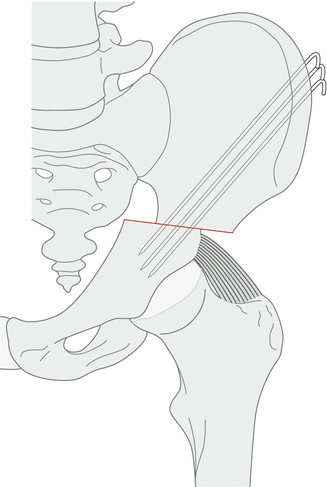

대부분 절골술은 Reconstructive osteotomy 이며 Chiari, Shelf 절골술이 salvage osteotomy 입니다. salvage osteotomy는 지붕 혹은 가벽을 만들어 준다는 식으로 생각하면 쉽습니다. 체중부하 면적을 증가시켜 줄 수 있습니다.

1. Salter 는 Acetabular index 가 10~15도 이하로 변형이 심하지 않을 때 사용할 수 있습니다. symphysis pubis를 hinge로 하여(chiari osteotomy와 hinge가 같습니다.) anterolateral을 덮어줄 수 있습니다. 단순하게 방향을 교정해주기 때문에 비구의 변형이 있는 경우 잘 사용하지 않습니다.